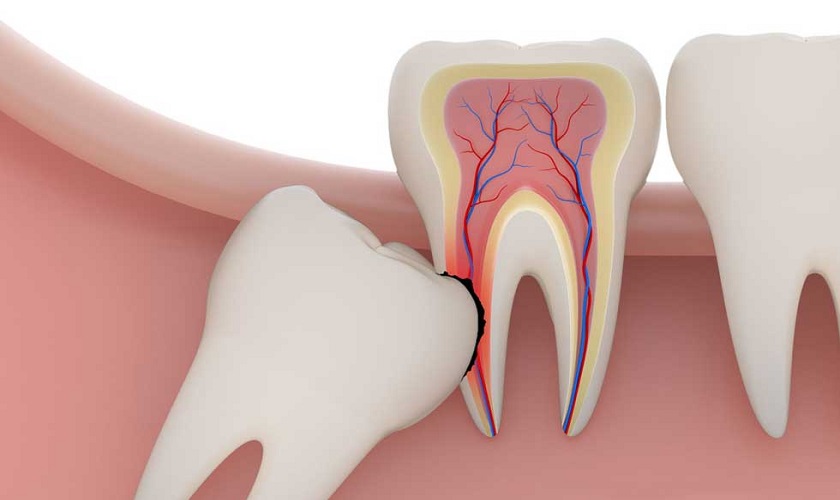

Mặt khác, khi mọc đầy đủ tất cả các răng thì các răng mọc sau cùng thường không có đủ diện tích trống để mọc lên. Đây là lí do vì sao tình trạng răng khôn mọc lệch, mọc ngầm xảy ra rất thường xuyên và gây ảnh hưởng rất lớn tới các răng kế cận trên cung hàm.

Răng khôn mọc lệch là tình trạng rất hay gặp phải<